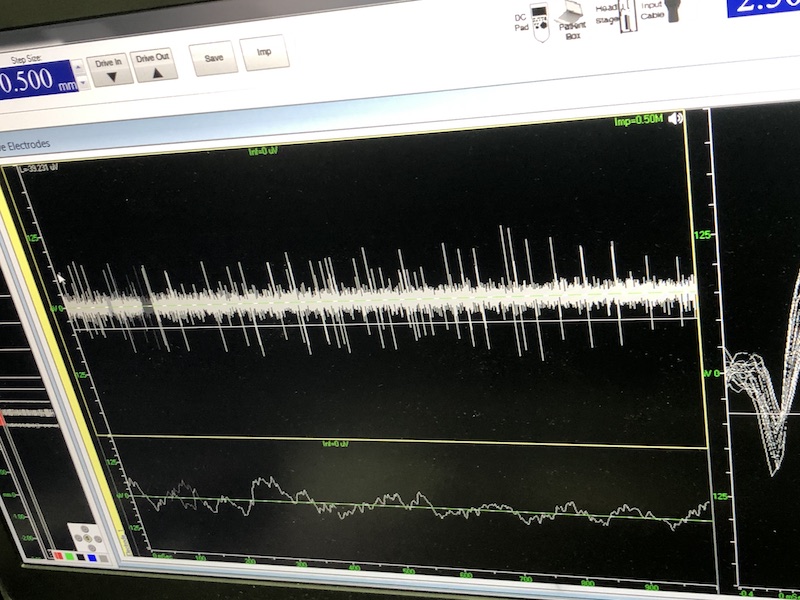

與此同時(shí),檢測電極實(shí)時(shí)記錄電極末端每一點(diǎn)處的電信號,當(dāng)電極逐漸接近手術(shù)規(guī)劃靶點(diǎn)時(shí),借助電信號的特征,醫(yī)生可以判斷電極是否已經(jīng)沿長軸植入患者顱內(nèi)的目標(biāo)核團(tuán),以及植入的準(zhǔn)確長度。下圖中,檢測信號屬于典型的核團(tuán)信號,證明電極已經(jīng)抵達(dá)相對理想的植入位置,記錄下此刻的位置后,即可在相應(yīng)位置植入刺激電極。

檢測核團(tuán)信號